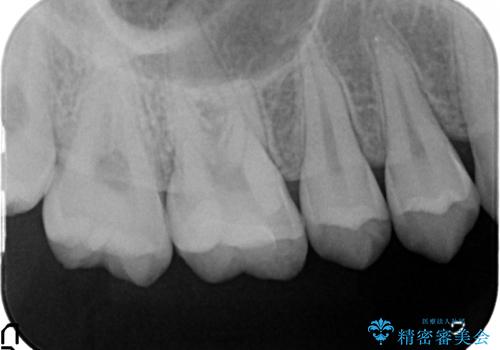

検診による初期虫歯の早期発見・早期治療

- 検診を希望され来院されました。

症状は特にありませんでしたが、検診で全体をチェックすることで虫歯を小さなうちに早期発見し治療することができました。

- 7万円 (emaxインレー)費用は治療当時の料金となります